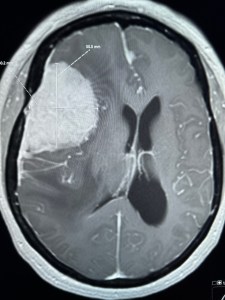

My MRI this past Monday revealed a 6cm brain tumor. They think it’s benign but won’t know until they go in. I need two surgeries. One to sever blood supply to the tumor and then weeks later its removal. For those interested, here is the scan.